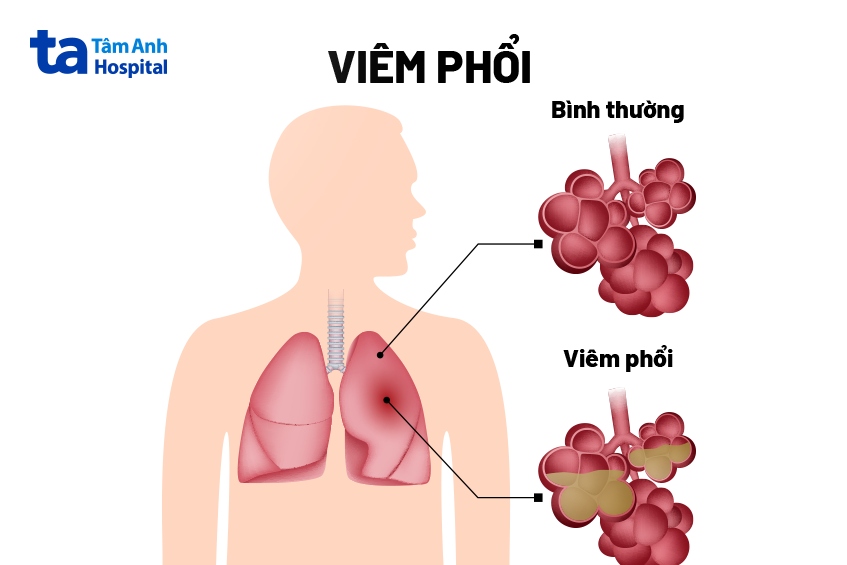

Đây là biến chứng phổ biến và nghiêm trọng của bệnh. Khi virus hoặc vi khuẩn xâm nhập vào phổi qua đường hô hấp. Trong quá trình nhiễm trùng các mô phổi bị viêm nhiễm gây ra tình trạng sưng tấy, phù nề, điều này làm giảm khả năng trao đổi khí gây ra hiện tượng sốt cao, ho nhiều đau ngực và khó thở. Viêm phổi do ho gà thường biến chứng nhanh và có thể dẫn đến suy hô hấp hoặc nhiễm trùng máu đe dọa tính mạng của người bệnh.